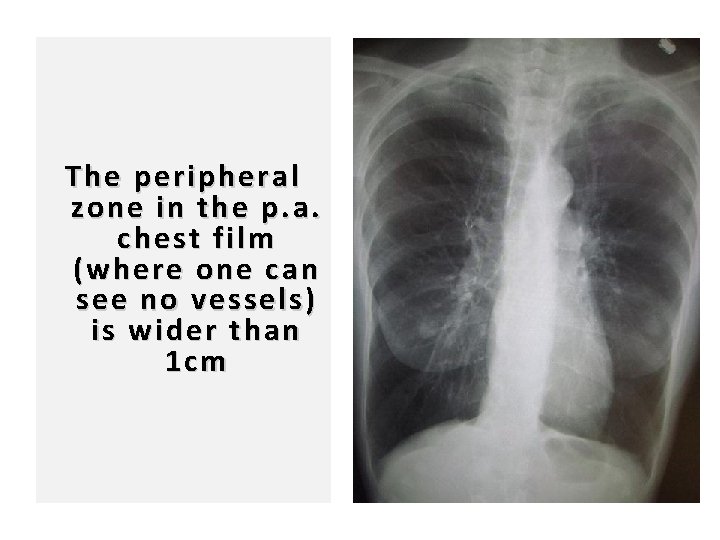

97 The peripheral zone in the p. a. chest film (where one can see no vessels) is wider than 1 cm